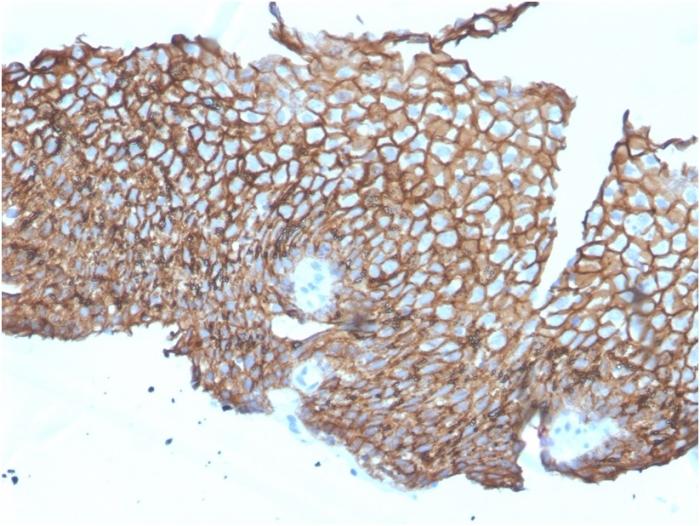

Recognizes a protein of 130 kDa, identified as Desmoglein-3 (DSG3). This MAb is highly specific to Desmoglein-3 and does not cross-react with other members of the Desmoglein-family. DSG3 is a calcium-binding transmembrane glycoprotein component of desmosomes in vertebrate epithelial cells. Research has shown that DSG3 has a very high sensitivity (80%) and specificity (100%) in recognizing squamous cell carcinoma (SqCC). Therefore, DSG3 is considered a very important marker for lung SqCC and can be a useful ancillary marker to separate SqCC from other subtypes of lung cancer. Moreover, studies have shown that DSG3 expression in lung SqCC may indicate a poor prognosis. Primary antibodies are available purified, or with a selection of fluorescent CF® Dyes and other labels. CF® Dyes offer exceptional brightness and photostability. Note: Conjugates of blue fluorescent dyes like CF®405S and CF®405M are not recommended for detecting low abundance targets, because blue dyes have lower fluorescence and can give higher non-specific background than other dye colors.

Positive Control

A431 cells. Skin or Lung Squamous Cell Carcinoma (SCC).

Antibody target cellular localization

Plasma membrane

Cell tissue expression

Epidermal cells

Tumor expression

Squamous cell carcinoma